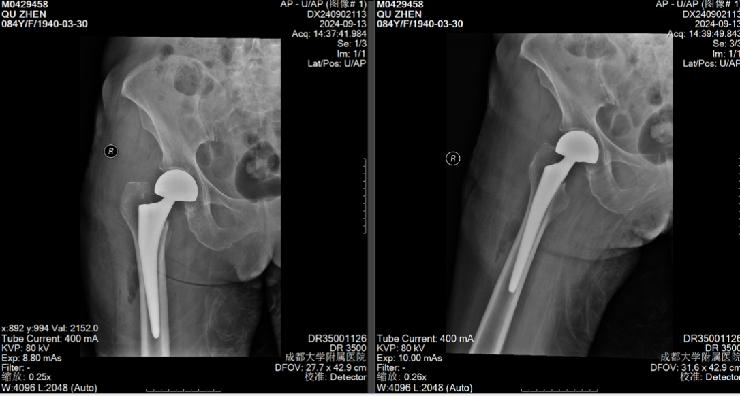

2024年9月2日这天,地处高原的石渠已有了丝丝凉意,成大附院“组团式”帮扶石渠县人民医院医疗队的骨科主治医师徐锴接诊了一位84岁藏族老人,1天前在家中摔倒后不能站立,X片提示为右侧股骨颈骨折(Garden III型)。经充分评估病情后,考虑石渠县医疗条件有限,无法保障患者手术期生命安全,徐锴遂与远在千里之外的成大附院本部骨科主任医师员晋联系,说明老人情况后,作为金牛区政协委员、医卫界召集人的员晋主任医师当即为该患者联系转诊事宜,为患者的后续治疗积极准备。石渠医疗条件欠缺,所幸石渠县人民医院与成大附院建立了快速响应转诊机制,为患者得到有效治疗争取了宝贵时间,为患者的后期恢复创造了良好条件。

患者入院后,骨科员晋主任医师团队何嘉尧、周浩、李济渊医师各司其职,迅速评估患者病情并积极治疗,启动院内MDT多学科会诊,由麻醉手术中心、心血管内科、呼吸与危重症医学科、感染性疾病科、重症医学中心、肝胆外科、消化内科、肾病风湿免疫科、临床营养科等专家对患者病情充分评估后,建立起一整套完整的针对该患者的围手术期管理方案。在予以保肝、护肾、利尿、抗凝、抗感染、调节电解质平衡、营养支持等多维度处理后,患者病情趋于稳定,择期为患者行右侧人工髋关节置换手术。

手术方案与患者及家属进行了耐心详细的沟通讲解并取得患者及家属的同意。具有数十年关节手术经验的“金牛工匠”员晋主任医师团队凭借娴熟的技艺和丰富的经验,顺利完成了手术。术后患者恢复情况良好,避免了长期卧床可能带来的并发症。